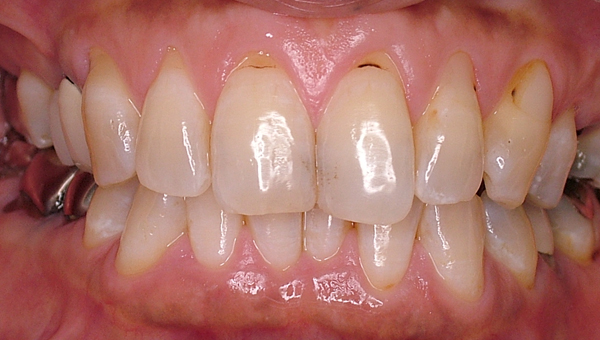

セラミッククラウン前

セラミッククラウン後

前歯を白くしたいという希望で来院

上の前歯6本をジルコニアクラウン(レイヤリングテクニック)にて補綴処置。

歯周病治療(歯石除去、歯ブラシ指導)

治療期間 3か月

治療費 720,000円+消費税

副作用 知覚過敏、歯肉炎